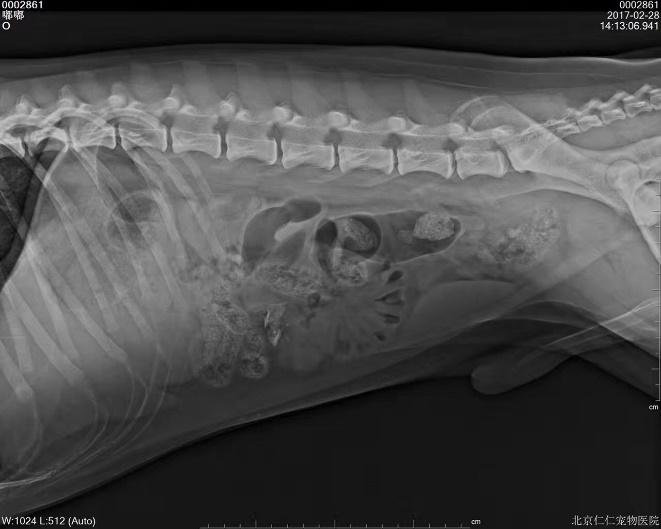

c.X线检查。对于阻线性较强的物质(如金属、骨头)较容易辨别,对于阻线性与组织密度相似的物体较难确定,但是可以通过消化道灌服造影剂判断是否有阻塞或可包裹物体。

机械性肠梗阻的读片要点:1.体积增大;2.形态轮廓变化;3.影像密度变化;4.浆膜细节变化。

金毛 线性异物

d.超声检查。消化道超声部分属于其他范畴,此处不做赘述。能够识别肠套叠即可。

肠套叠,可见肠道内容物有肠道分层结构